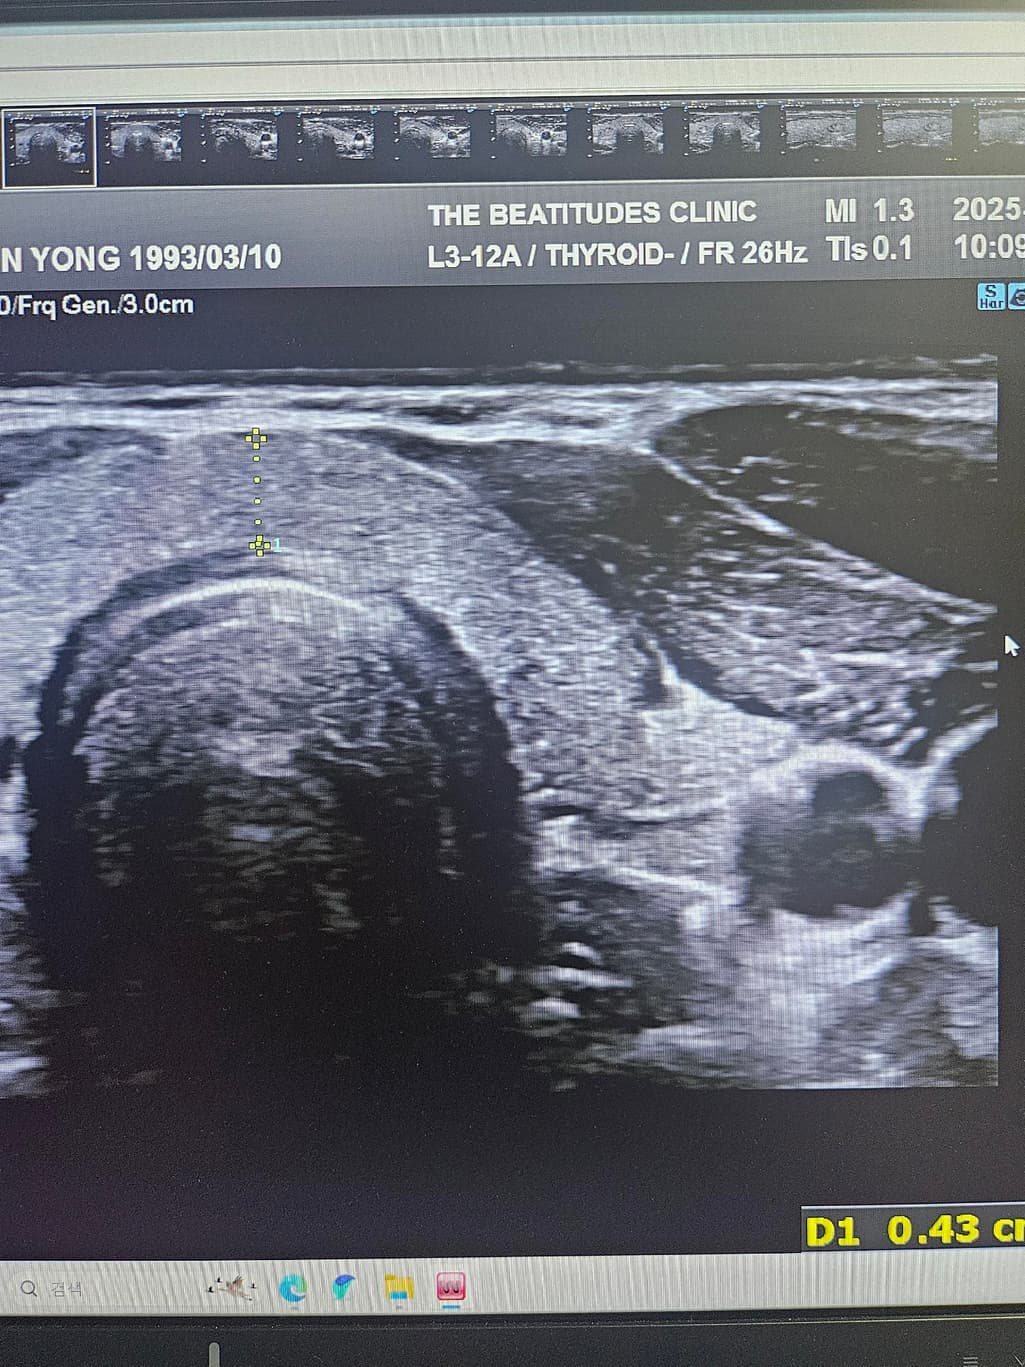

갑상선초음파하고 세침검사 권유받았는데 위의 세개의 사진은 같은 혹이 맞는건가요? 1개 있다고 얘기해줘서 봤는데 사이즈가 이렇게나와서 가로 세로 폭 값인건지 여쭤보고싶습니다

첫번째 사진과 세번째 사진의 경우 같은 결절로 보입니다.

두번째 사진의 경우는 결절이 보이지 않으며 협부의 두께를 측정한 것 같습니다.

모양만 본다면 갑상선암이 많이 의심되는 상황은 아닙니다.

단지 3번째 사진의 경우 크기가 기재되어 있지 않기 때문에

크기만으로 따진다면 이는 애매하다 할 수 있겠습니다.

초음파에서 첫번째, 세번째 사진의 급성 연골 오른쪽에 위치한 오른쪽 갑상선에 동그란 혹이 관찰되며 사진으로는 사이즈를 정확하게 구하기 어렵지만 1.5 cm 이상으로 보이며 혹 안에 균질하지 않은 모습으로 악성 혹은 양성이라고 해도 정기적으로 관찰해야 하는 종양으로 보여 조직 검사를 받는 것은 필요한 것으로 보입니다. 갑상선 종양은 다른 종양에 비해 예후가 좋아 적절한 치료를 받으면 대부분 완치가 가능합니다